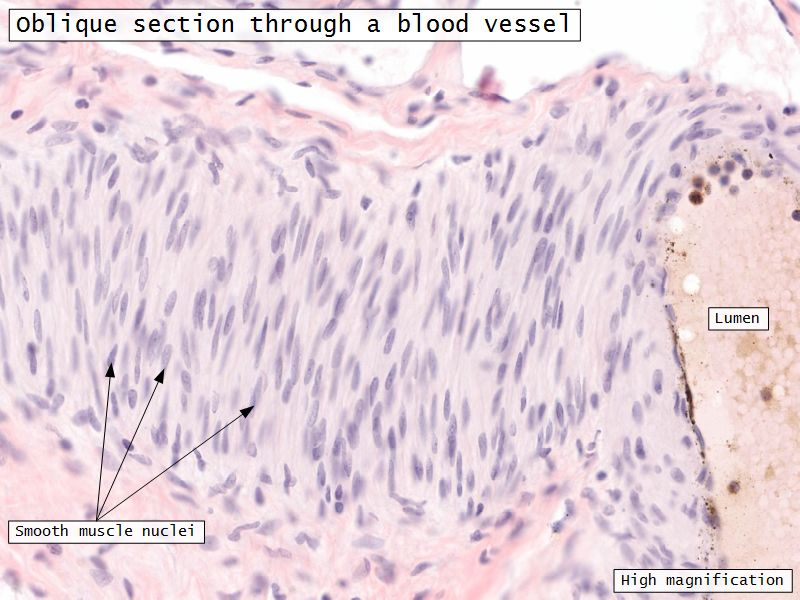

- 3 layers indistinct smooth

- Inner longitudinal/oblique

- Central circular

- Large blood vessels

- Stratum vasculare

- Outer longitudinal/oblique